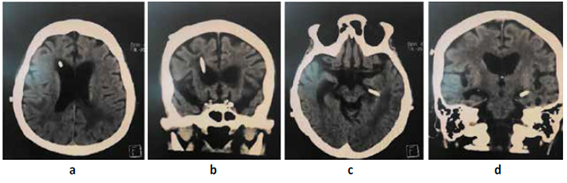

Paciente mujer de 73 años natural de Lima Perú con tiempo de enfermedad de 2 meses caracterizado por trastorno del sensorio, vómitos, cefalea y alteración de marcha; al examen físico neurológico se evidencia desorientación, hemiparesia derecha a 2/5 (Escala de Daniels), Babinsky derecho (+) Hoffmann derecho (+), parálisis facial central izquierda. motivo por el cual se realiza resonancia magnética cerebral (RMN) con contraste (c/c) evidenciando lesiones de aspecto nodular que comprometen ventrículos laterales, con extensión al III Y IV ventrículo, condicionando edema perilesional e hidrocefalia con signos de efecto hipertensivo Figura N°1; Se decide manejo quirúrgico de emergencia colocación de un sistema de derivación ventrículo peritoneal bilateral Figura N°2 y N°3. Ya con el paso de los días y mejoría del cuadro de hipertensión endocraneana resuelto se decide realizar biopsia guiada por estereotaxia obteniéndose por resultado de anatomía patológica proceso linfoproliferativo de células redondas atípicas correspondientes a células B maduras. Motivo por el cual se decide tratamiento oncológico con uso de radioterapia (10 sesiones) y corticoides que se realiza durante 3 meses; Es dada de alta con mejoría clínica. Al cabo de 4 meses el paciente acude para su control, se realiza tomografía cerebral (TEM) sin contraste (SC)Figura N°3evidenciando ausencia casi total de la tumoración y mejoría de los síntomas.